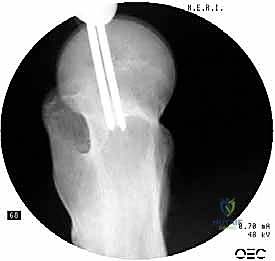

1. المسمار النخاعي الرئيسي (Intramedullary Nail): مسمار طويل يمتد داخل القناة النخاعية لعظمة الفخذ.

2. المسمار الرأسي/العنقي (Cephalic/Lag Screw): مسمار سميك وقوي يمر من خلال الجزء العلوي للمسمار النخاعي، ويدخل في عنق ورأس عظمة الفخذ لتثبيت الكسر الرئيسي.

3. مسامير الغلق السفلية (Distal Locking Screws): مسامير صغيرة تُثبت أسفل المسمار النخاعي لمنعه من الدوران أو الانزلاق داخل العظم.

هذا التصميم العبقري يجعله أقوى نظام تثبيت متوفر حالياً، حيث يمر محور تحمل الوزن عبر المسمار الموجود داخل العظم، مما يجعله مقاوماً للكسر والانحناء، ويسمح للمريض بالاعتماد على ساقه في وقت قياسي.